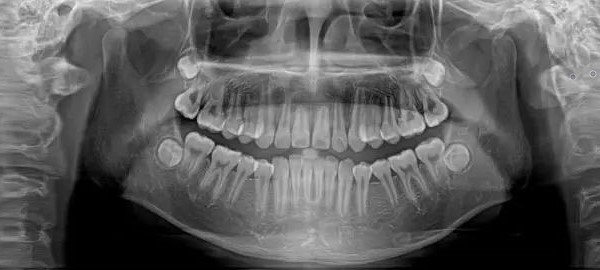

全景片是什么?全景片就是可以在一张胶片上可以完整、清晰地显示上颌骨、下颌骨全貌,上下颌牙列情况,牙槽骨情况能清晰显示上颌窦腔、窦壁、窦底情况,以及颞颌关节情况并对颌骨周围疾病的诊断提供帮助。

因为全景片可以确定测定牙齿倾斜角度、牙周软组织情况、牙根情况、牙槽骨质情况,解剖形态的精确测量为医生术前的诊断分析与设计提供全景样图像依据,口腔医生借此能更好地为患者设计治疗方案。

拍摄全景片是口腔治疗之前很重要的一个检查过程,医生通过全景片可以观察到牙齿的健康状况,是否有隐形龋齿、埋伏阻生牙、多生牙、牙槽骨吸收、牙龈萎缩、口腔内是否有瘤体等。在做牙齿种植、牙齿矫正、牙齿修复、智齿拔除等之前均需要拍摄口腔全景片。

①牙齿的解剖结构、密度,牙周状况的检查。②埋藏牙定位及周边相邻关系判断。③牙齿发育情况判断。④牙齿矫正前的病例分析、测量,指导矫正方案的制定。⑤种植前牙槽骨的质、量的评价及种植体大小、长短的确定。

⑥牙列缺失复杂修复前基牙的评估。⑦头面部外伤、骨折的诊断。⑧根管充填、镶牙、种植、矫正效果的复查、评估。⑨智齿拔除等外科手术方案制定和风险评估。⑩头、面部肿瘤、囊肿的筛查,鉴别。